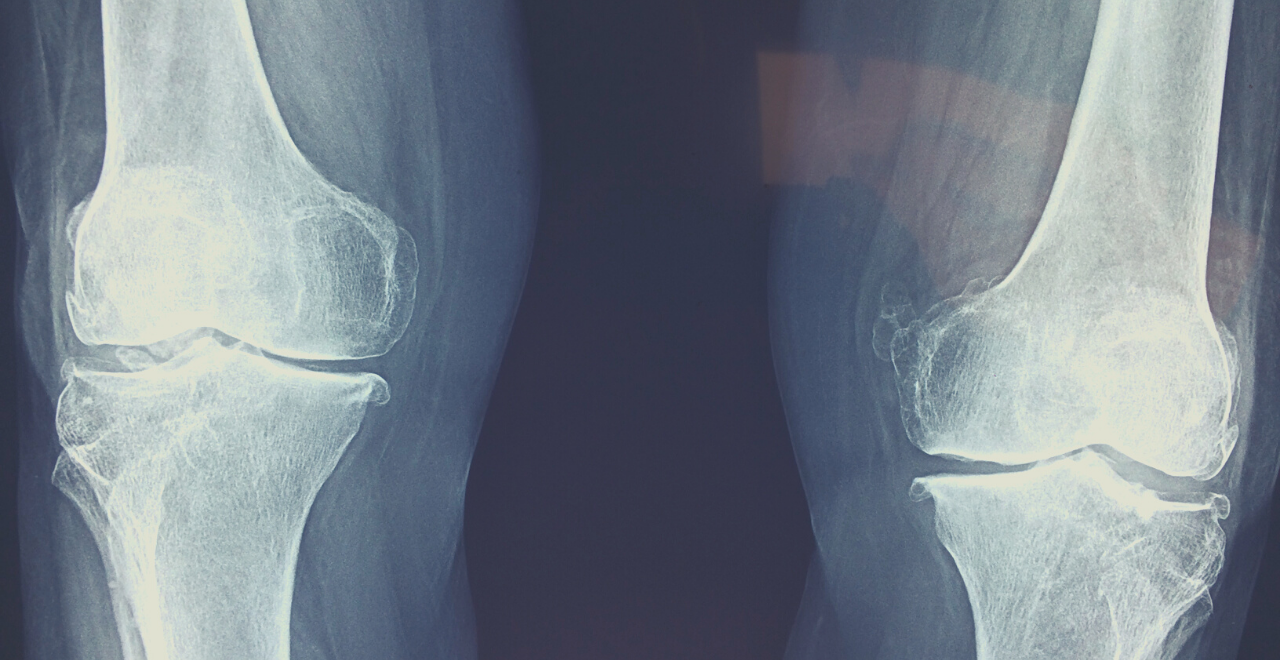

Un tempo si usava molto il detto “avere le ossa dure” per dire di qualcuno che è ben resistente alle avversità e ai colpi della sorte.

Ho sempre creduto che nei detti popolari ci sia molta più saggezza di quanto si possa pensare: infatti chi si ammala di osteoporosi spesso accusa di non riuscire più a far fronte alle situazioni difficili, al peso dell’età e di ciò che comporta. Il corpo “non regge più”, e questo si manifesta fisicamente con ossa che non svolgono più al meglio la loro funzione di sostegno.

Le cadute spesso avvengono in realtà dopo che l’osso si rompe!

Molti di noi credono il contrario, ovvero che la rottura dell’osso sia associata alla caduta, ma non è così. Infatti la caduta è una conseguenza, poiché l’osso diventa talmente sottile e poroso da spezzarsi solo.